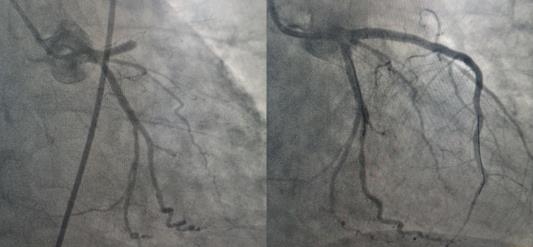

10:10患者到達延安大學咸陽醫院,剛將患者從救護車推下進入門診大廳,患者突然出現意識喪失,觸摸大動脈搏動消失,心電監護提示室性心動過速,危急時刻,延安大學咸陽醫院胸痛中心楊飛娟主治醫師、謝昕護士、王丹丹護士協同涇陽縣醫院尹夢肖主治醫師、張陽陽護士立即就地搶救,門診梁田副主任醫師及胸痛中心二線李新國主任也聞訊趕來支援。經過3次電除顫及胸外按壓后患者恢復竇性心律,意識好轉。在場醫務人員立即將患者送至導管室,實施急診PCI,于10:57開通閉塞血管,恢復血流,將危在旦夕的夏大叔從鬼門關搶救回來。目前患者正在進一步康復中。